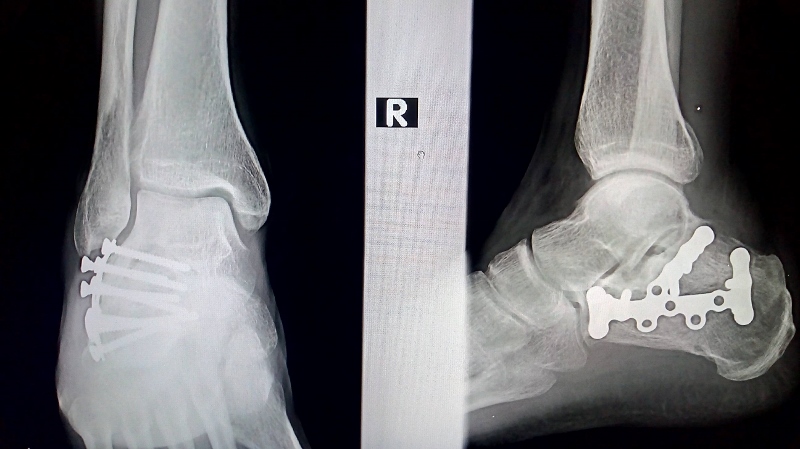

Sudbina se opasno poigrala sa našim Dedom koji je 16.04. ove godine slomia obe pete i desnu ruku u banalnoj situaciji koja nije imala veze sa penjanjem. Kako kaže, priko noći mu je umisto projektiranja 8b-ova, glavni projekt posta samostalno se popet na wc školjku. Ipak, Deda je bia i osta vanserijska klasa, niti 5 miseci od ozljede, pun željeza i vidno šepajući, as je već uknjižia 2x7c, 1x7c+, 1x8a i 1x8a+. Da stvar bude luđa među spomenutima je i Kacot (7c) u Velikoj rupi Markezine grede, vrhunska ali rijetko ponavljana linija, kontrovezna gotovo ka La vie en rose (Brčko-Banovići) na istočnom dilu Grede. As je u Kacot uložia samo 3 ulaska, šta je Did samo kratko prokomentira sa "Sve mi je jasno!", dok se baba znakovito nasmijala.